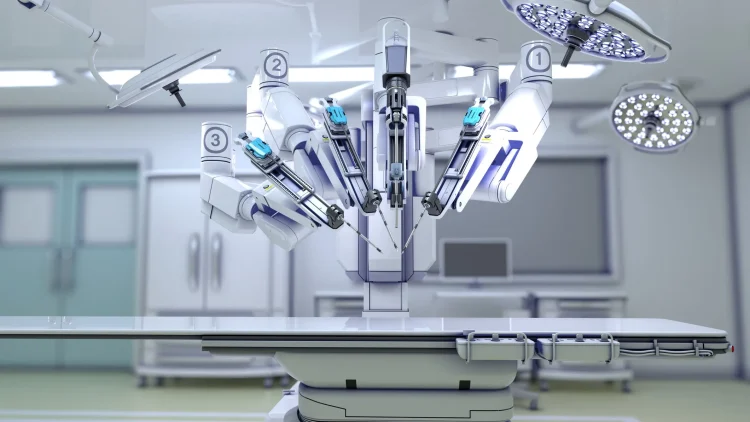

Computer-Assisted Navigation – Another advancement in orthopedics is computer-assisted navigation. Navigating in real time requires the best possible information about the patient’s anatomy. Computer-assisted navigation aids in providing accurate and detailed images to physicians on their screens. These images are used to plan surgeries before they happen.

Preoperative Planning Software – Preoperative planning software provides surgeons with an image of the patient’s anatomy before the procedure. This gives surgeons a virtual tour of the area of interest and provides them with a reference point for the best location to make incisions.

Image-guided surgery is a method that uses medical imaging technology to help surgeons plan their procedures before surgery. It can be used for any orthopedic procedure including hip replacement, knee replacement, shoulder procedures, spine procedures, and other surgical procedures where the precision of incision placement and accuracy are critical.

Image-guided surgery uses computer navigation systems to create three-dimensional images of the patient’s anatomy. These images allow the surgeon to plan the best approach, minimize invasive techniques, and accurately perform the surgery.

Today, advanced image-guided technologies offer real-time feedback to the surgeon and improve the accuracy of incision placement. These tools also reduce radiation exposure, increase operating efficiency, and shorten hospital stays.

Advantages of image-guided surgery include less pain, fewer complications, faster recovery times, decreased risk of infection, shorter hospital stays, and improved cosmetic outcomes. These advantages have been demonstrated in numerous studies.

Orthopedic surgeons have embraced image-guided surgeries, and many hospitals now employ at least one trained specialist who performs these techniques.